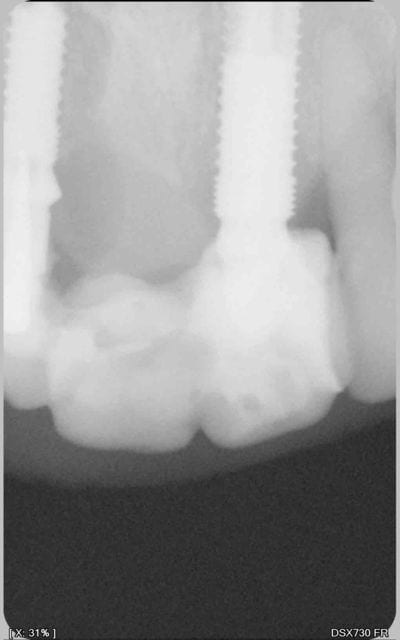

27/04/2011 à 10h26

désolé pour le retard, voici la radio,

je ne sais pas si les piliers provisoires seront réutilisable dans le pire des cas...

yann7

27/04/2011 à 10h28

c mieux comme ca